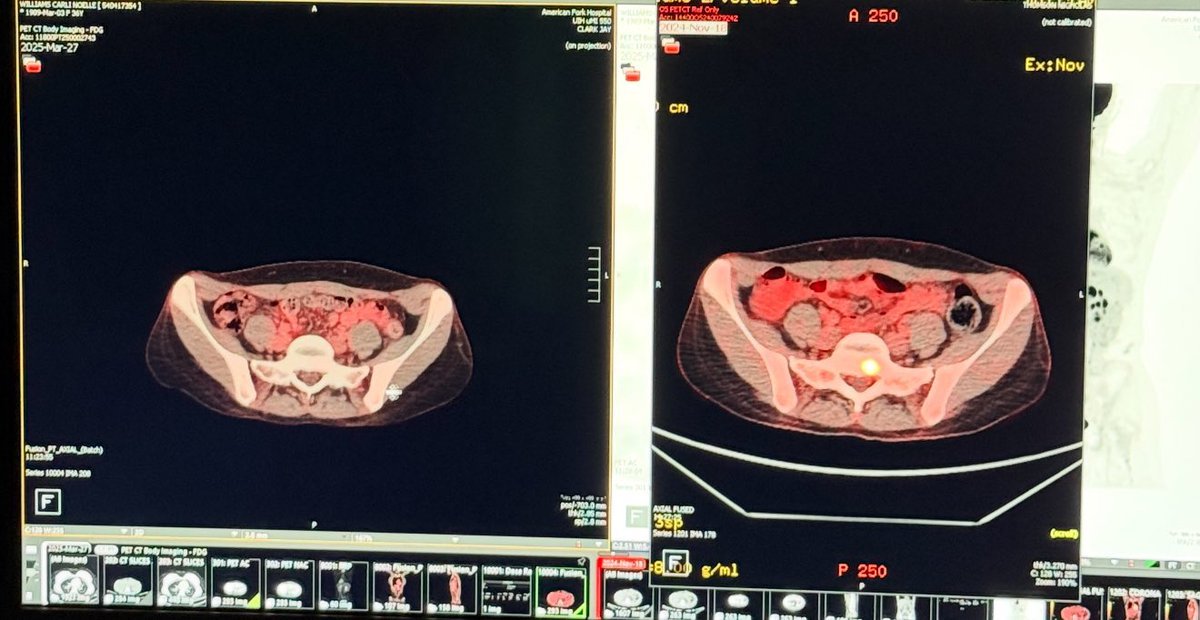

The scan on the right is from November and showed stage IV breast cancer in my wife’s spine. The scan on the left is from yesterday and shows “No Evidence of Disease.”

Following every protocol from the oncologist left my wife exhausted and suicidal (plus the cancer came back anyway) so we started doing our own research... See more